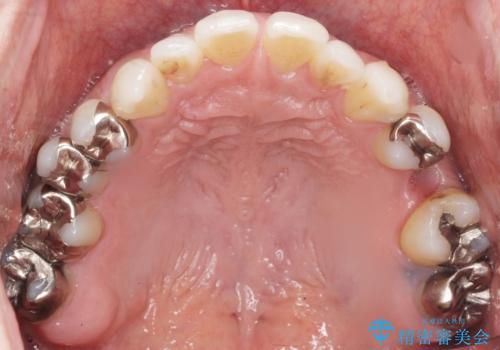

- 奥歯のかぶせ物が土台ごとはずれてしまったことを主訴に来院された患者様です。

残根状態になっている左上の小臼歯(左上5)を精査したところ、う蝕が歯肉縁下まで進行しており保存不可能な状態でした。

患者様のご希望により、抜歯後インプラント治療を行いました。